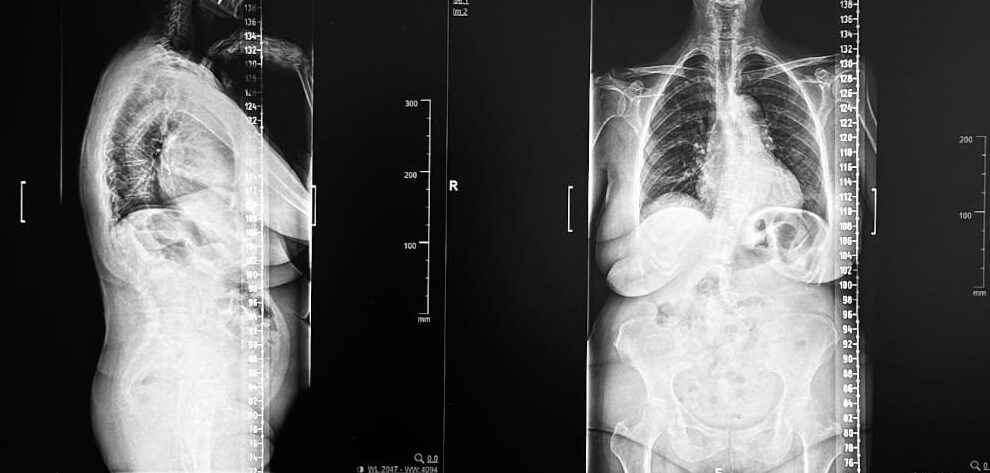

Escoliosis Lumbar del Adulto y Tratamiento Quirúrgico con Guías 3D

por marke153 | Dic 5, 2024 | Noticias

La escoliosis lumbar del adulto es una deformidad de la columna vertebral caracterizada por una desviación lateral en la región lumbar, que suele asociarse con desgaste degenerativo de los discos intervertebrales y las articulaciones facetarias. Este trastorno puede...